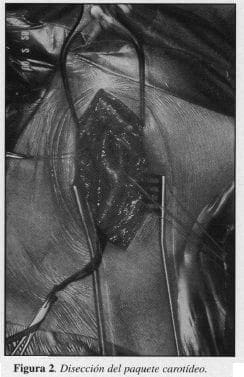

2. Disección del paquete vasculonervioso y de las carótidas primitiva, interna y externa (Figura 2).